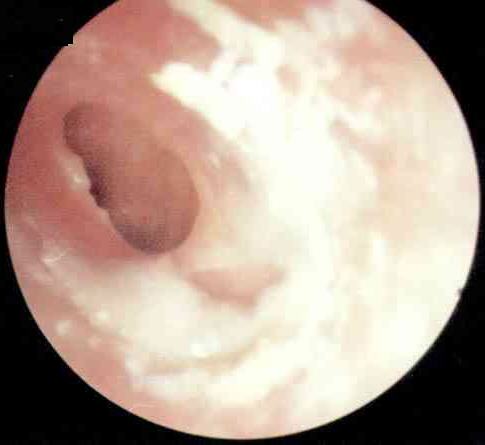

分泌性中耳炎病理图

耳朵通过咽鼓管与鼻咽部相通。咽鼓管可以调节耳内的压力,以此与大气压保持平衡,其外还有防御、清洁的功能。在秋冬季,日夜温差比较大,常会诱发上呼吸道感染,炎症波及咽鼓管时,耳内往往会形成负压,这时会产生耳闷的感觉。耳内的黏膜受负压影响分泌较多的液体,并由于咽鼓管功能障碍不能及时排出,积在耳内产生听力下降,耳朵里有水泡声,有时还会感到耳痛。